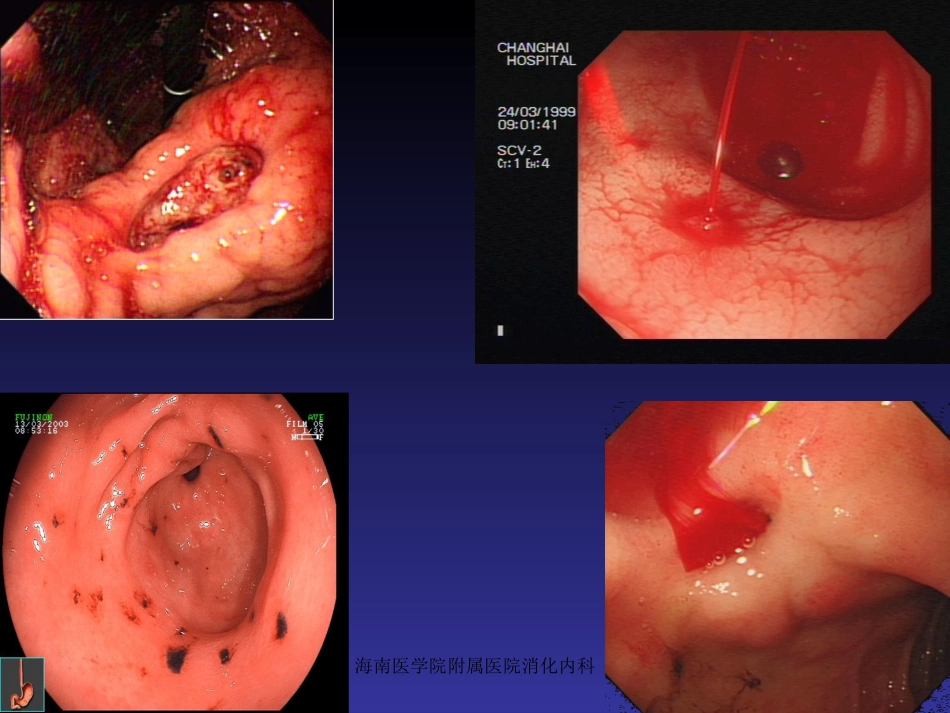

海南医学院附属医院消化内科•概述•胃、十二指肠出血分为:a)静脉曲张性出血b)非静脉曲张性出血消化性溃疡胃、十二指肠粘膜糜烂•非静脉曲肿瘤张性出血Dieculafoy氏溃疡血管畸形海南医学院附属医院消化内科海南医学院附属医院消化内科海南医学院附属医院消化内科海南医学院附属医院消化内科一.胃、十二指肠出血治疗方法•药物治疗•外科手术治疗•X线介入血管栓塞治疗•内镜下治疗内镜治疗优势:能够直观观察到胃、十二指肠出血部位,并能采取各种止血方法作相应止血治疗,从而避免以往常规外科手术治疗方法。海南医学院附属医院消化内科二、适应症与禁忌症适应症:•消化性溃疡并出血•Dieculafoy氏溃疡出血•急性胃粘膜病变并出血•血管畸形并出血•肿瘤并出血•Mallory-Weiss综合征•其他原因所致胃、十二指肠血管出血海南医学院附属医院消化内科禁忌症•胃镜检查禁忌者•失血性休克尚未纠正•安装心脏起搏器者禁忌高频电凝切除海南医学院附属医院消化内科三、术前准备•胃镜检查一般在出血4~48小时内进行。•如有休克,先抗休克治疗,待血压稳定后再胃镜检查和治疗。•如活动性出血可边输血、输液纠正休克,边准备急诊内镜治疗。•有严重并存疾病及老年患者等高危人群,经积极处理但血流动力学状态不稳定者,需考虑急诊内镜止血治疗。海南医学院附属医院消化内科•内镜治疗前应向病人家属做好解释工作,取得病人的配合,并履行知情同意书上签字手续。•在内镜操作过程中监测血压、心率、血氧饱和度。•术中可酌情静脉注射安定和654-2各10mg,并保持静脉通道开放。•以防止误吸发生,事前做好气管插管的准备工作。•对有高危人群或有心血管系统疾病者检查及治疗中均心电监护。海南医学院附属医院消化内科四、止血操作方法1、钛夹止血其原理:在内镜直视下对出血血管钳夹或周围组织夹闭缝合,利用其闭合产生机械性压迫达到止血目的。器械准备:a)电子胃镜b)钛夹Olympus的Clip-850c)钛夹置放器(投放器)海南医学院附属医院消化内科海南医学院附属医院消化内科海南医学院附属医院消化内科•操作方法及步骤•1)洗胃:如胃内出血部位血液或血凝块影响出血病灶视野,应插胃管用生理盐水洗尽胃内积血。•2)胃镜检查:寻找出血部位、病变范围、病变性质及有无活动性出血。•3)钛夹止血:将钛夹安装于投放器上,经内镜活检钳道插入,找到出血血管或部位后,助手后拉投放器外管,露出钛夹,再后拉手柄,使钛夹张开到最大程度,并可根据需要旋转钛夹方向,钛夹对准出血血管或组织后,助手用力后拉投放器手柄,使钛夹夹闭后再前推手柄,使两者脱离。多少取决于出血情况。海南医学院附属医院消化内科海南医学院附属医院消化内科海南医学院附属医院消化内科海南医学院附属医院消化内科•注意事项•1)溃疡并出血者应避免钳夹坏死组织。•2)选择钛夹金属片前端的角度应大于90度。•3)尽可能将显露血管与周围组织一起钳夹,以达到最理想的止血效果。海南医学院附属医院消化内科2、氩离子凝固治疗•原理:氩离子血浆凝固术(APC)是利用高频输出电极使流向电极末端2~10mm处的氩气离子化,氩离子可以导电,将氩离子束传送至靶器官,能使组织表面凝固,从而起到止血和破坏有关组织等治疗作用。海南医学院附属医院消化内科•器械准备•前视胃镜•氩离子发生器(APC300)•高频电发生器(EndoCutICC200)•APC探头(直径2.3mm长2.2mm)海南医学院附属医院消化内科电凝止血原理海南医学院附属医院消化内科电凝止血示意图海南医学院附属医院消化内科•操作方法与步骤•开氩离子器瓶的阀门,注满氩气,气流量为2L/分,APC功率设为50~60W。•胃镜下找到出血病灶后,将APC探头由活检钳钳道插入。•APC探头置于距出血部位2~3mm以内进行凝固治疗,直至组织发白凝固,出血停止。•胃镜下观察数分钟,确认渗血停止后退镜。海南医学院附属医院消化内科氩离子电凝止血海南医学院附属医院消化内科海南医学院附属医院消化内科3、微波凝固术•原理:内镜下微波凝固治疗是一种新技术,它是通过微波产生热效应使局部组织坏死及小血管痉挛、血管壁肿胀、内皮细胞破坏等导致血管内血栓形成,达到止血目的。...